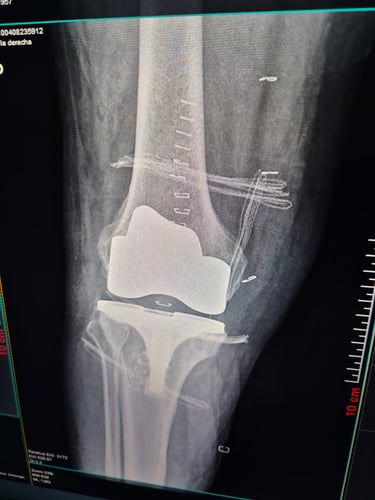

Cirugía de rodilla

Artritis y artrosis

Lesiones de meniscos y ligamentos (como LCA en rodilla)

Gallery

Provide a short description of the gallery, highlighting key things.